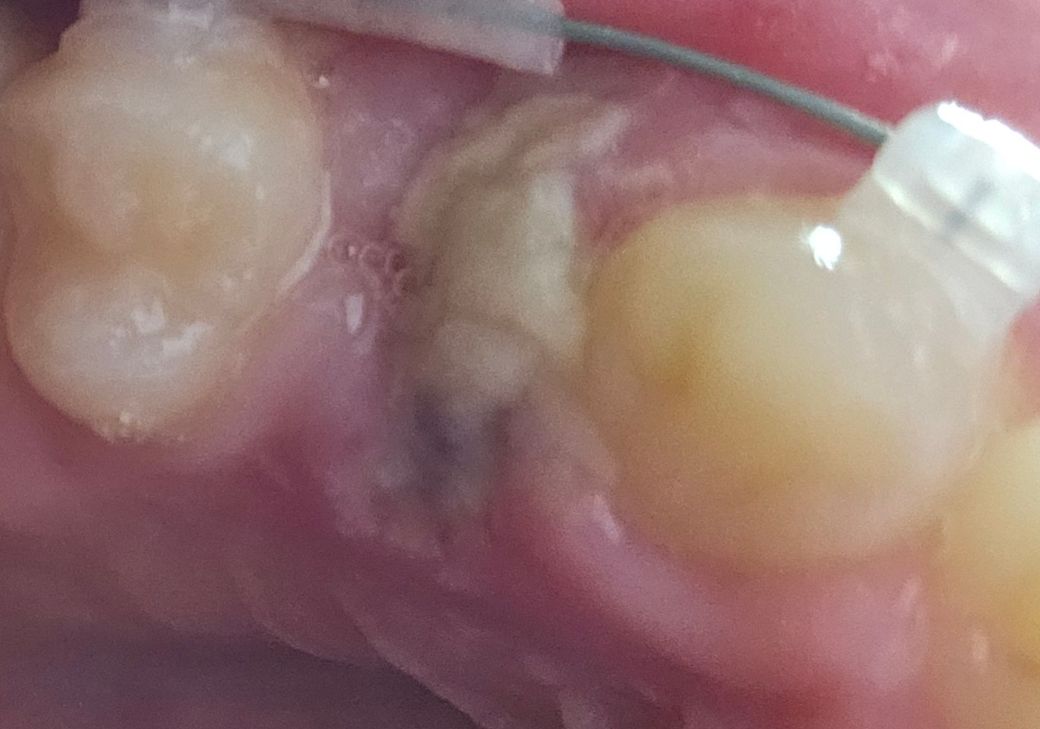

발치 부위 하얀색 덩어리 염증인가요?

교정 때문에 소구치 발치한지 3일 됐는데

사진처럼 하얀 덩어리같은 걸로 덮여있어요.. 음식물 찌꺼기는 아닌데 혹시 염증인가요?

• 1번 째 사진